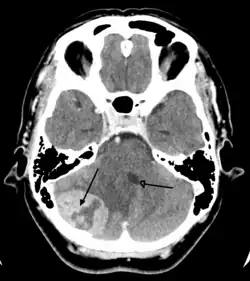

| Brain metastasis in the right cerebral hemisphere from lung cancer, shown on magnetic resonance imaging | |

A brain tumor (sometimes referred to as brain cancer) occurs when a group of cells within the brain turn cancerous and grow out of control, creating a mass. There are two main types of tumors: malignant (cancerous) tumors and benign (non-cancerous) tumors.[2] These can be further classified as primary tumors, which start within the brain, and secondary tumors, which most commonly have spread from tumors located outside the brain, known as brain metastasis tumors.[1] All types of brain tumors may produce symptoms that vary depending on the size of the tumor and the part of the brain that is involved.[2] Where symptoms exist, they may include headaches, seizures, problems with vision, vomiting and mental changes.[1][2][7] Other symptoms may include difficulty walking, speaking, with sensations, or unconsciousness.[1][3]

Secondary, or metastatic, brain tumors are about four times as common as primary brain tumors,[2][10] with about half of metastases coming from lung cancer.[2] Primary brain tumors occur in around 250,000 people a year globally, and make up less than 2% of cancers.[3] In children younger than 15, brain tumors are second only to acute lymphoblastic leukemia as the most common form of cancer.[11] In New South Wales, Australia in 2005, the average lifetime economic cost of a case of brain cancer was AU$1.9 million, the greatest of any type of cancer.[12]

Secondary tumors of the brain are metastatic and have spread to the brain from cancers originating in another organ. Metastatic spread is usually by the blood. The most common types of cancers that spread to the brain are lung cancer (accounting for over half of all cases), breast cancer, melanoma skin cancer, kidney cancer and colon cancer.[62]